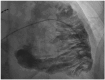

A 76-year-old male patient presented to the emergency room with acute decompensated right heart failure and presyncope episodes. Upon admission, his electrocardiogram (ECG) showed sustained monomorphic ventricular tachycardia at 180 bpm, which was electrically cardioverted, and the patient was subsequently admitted to the intensive care unit. The echocardiography showed a very dilated right ventricle (RV) with global systolic dysfunction and akinetic anterior and lateral walls. The coronary angiography was normal. The cardiac magnetic resonance showed signs of fibro-fatty replacement of the RV myocardium. Furthermore, the ECG after cardioversion showed inverted T waves and an epsilon wave in V1-V3 leads and late potentials by signal-averaged ECG. As such, a diagnosis of arrhythmogenic right ventricular cardiomyopathy (ARVC) was suspected. However, he presented no familial history of ARVC, was 76 years of age at the time of diagnosis and was asymptomatic until now. Given these considerations, we performed a right ventricular angiography which showed dilatation of the RV with akinetic/dyskinetic bulging, creating the "pile d'assiettes" image suggestive of ARVC. In the case of this patient, the RV angiography contributed to establish a diagnosis of ARVC with a very late presentation, to our knowledge the latest presentation in terms of age described in the literature.